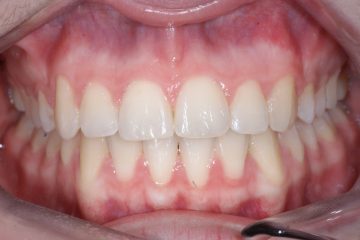

Correction d’une malocclusion de type Classe II division 1, surplomb horizontal inadéquat et chevauchement modéré aux 2 arcades. Des appareils fixes (broches et vis d’expansion) et des élastiques furent nécessaires pour améliorer ce sourire. Traitement chez une adolescente, réalisé en 18 mois.